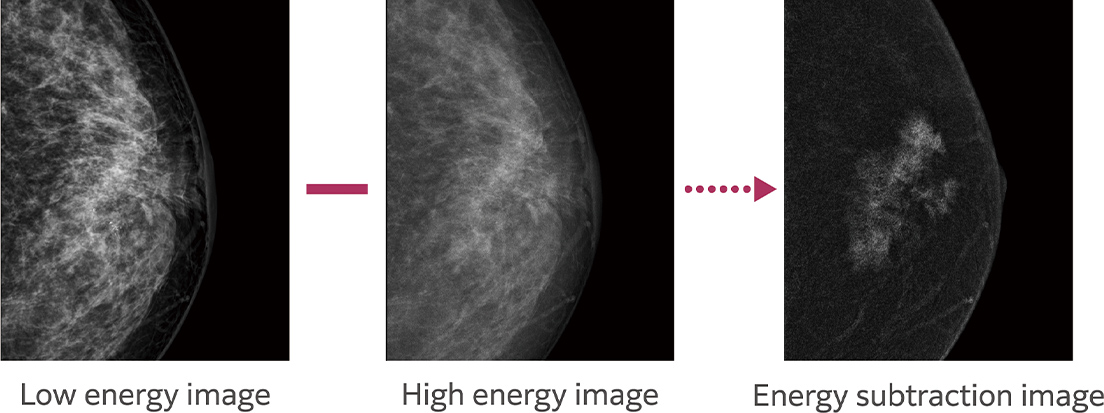

With one compression, it continuously performs low tube voltage (low energy) imaging close to the conventional mammography imaging and high tube voltage (high energy) imaging with a Cu filter, and automatically generates and displays a subtraction image of the obtained images.